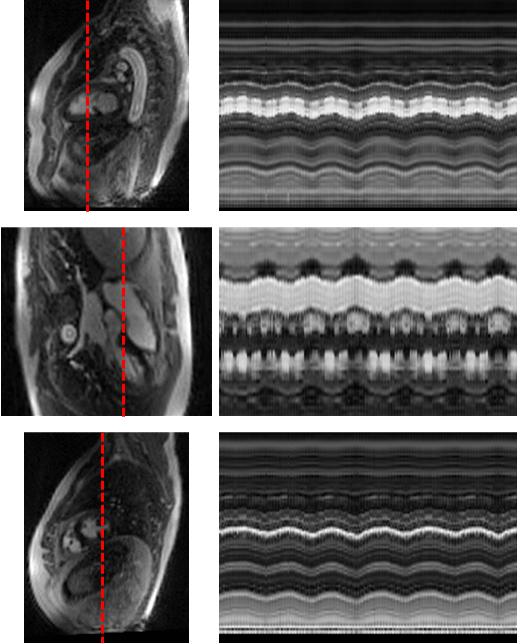

Figure 3. Spatiotemporal profile along the red cut line across 250 frames. Both cardiac motion and respiratory motion are clearly visible in healthy volunteer. The data were acquired under free-breathing conditions, resulting in smooth and regular cardiac and respiratory waveforms..png)